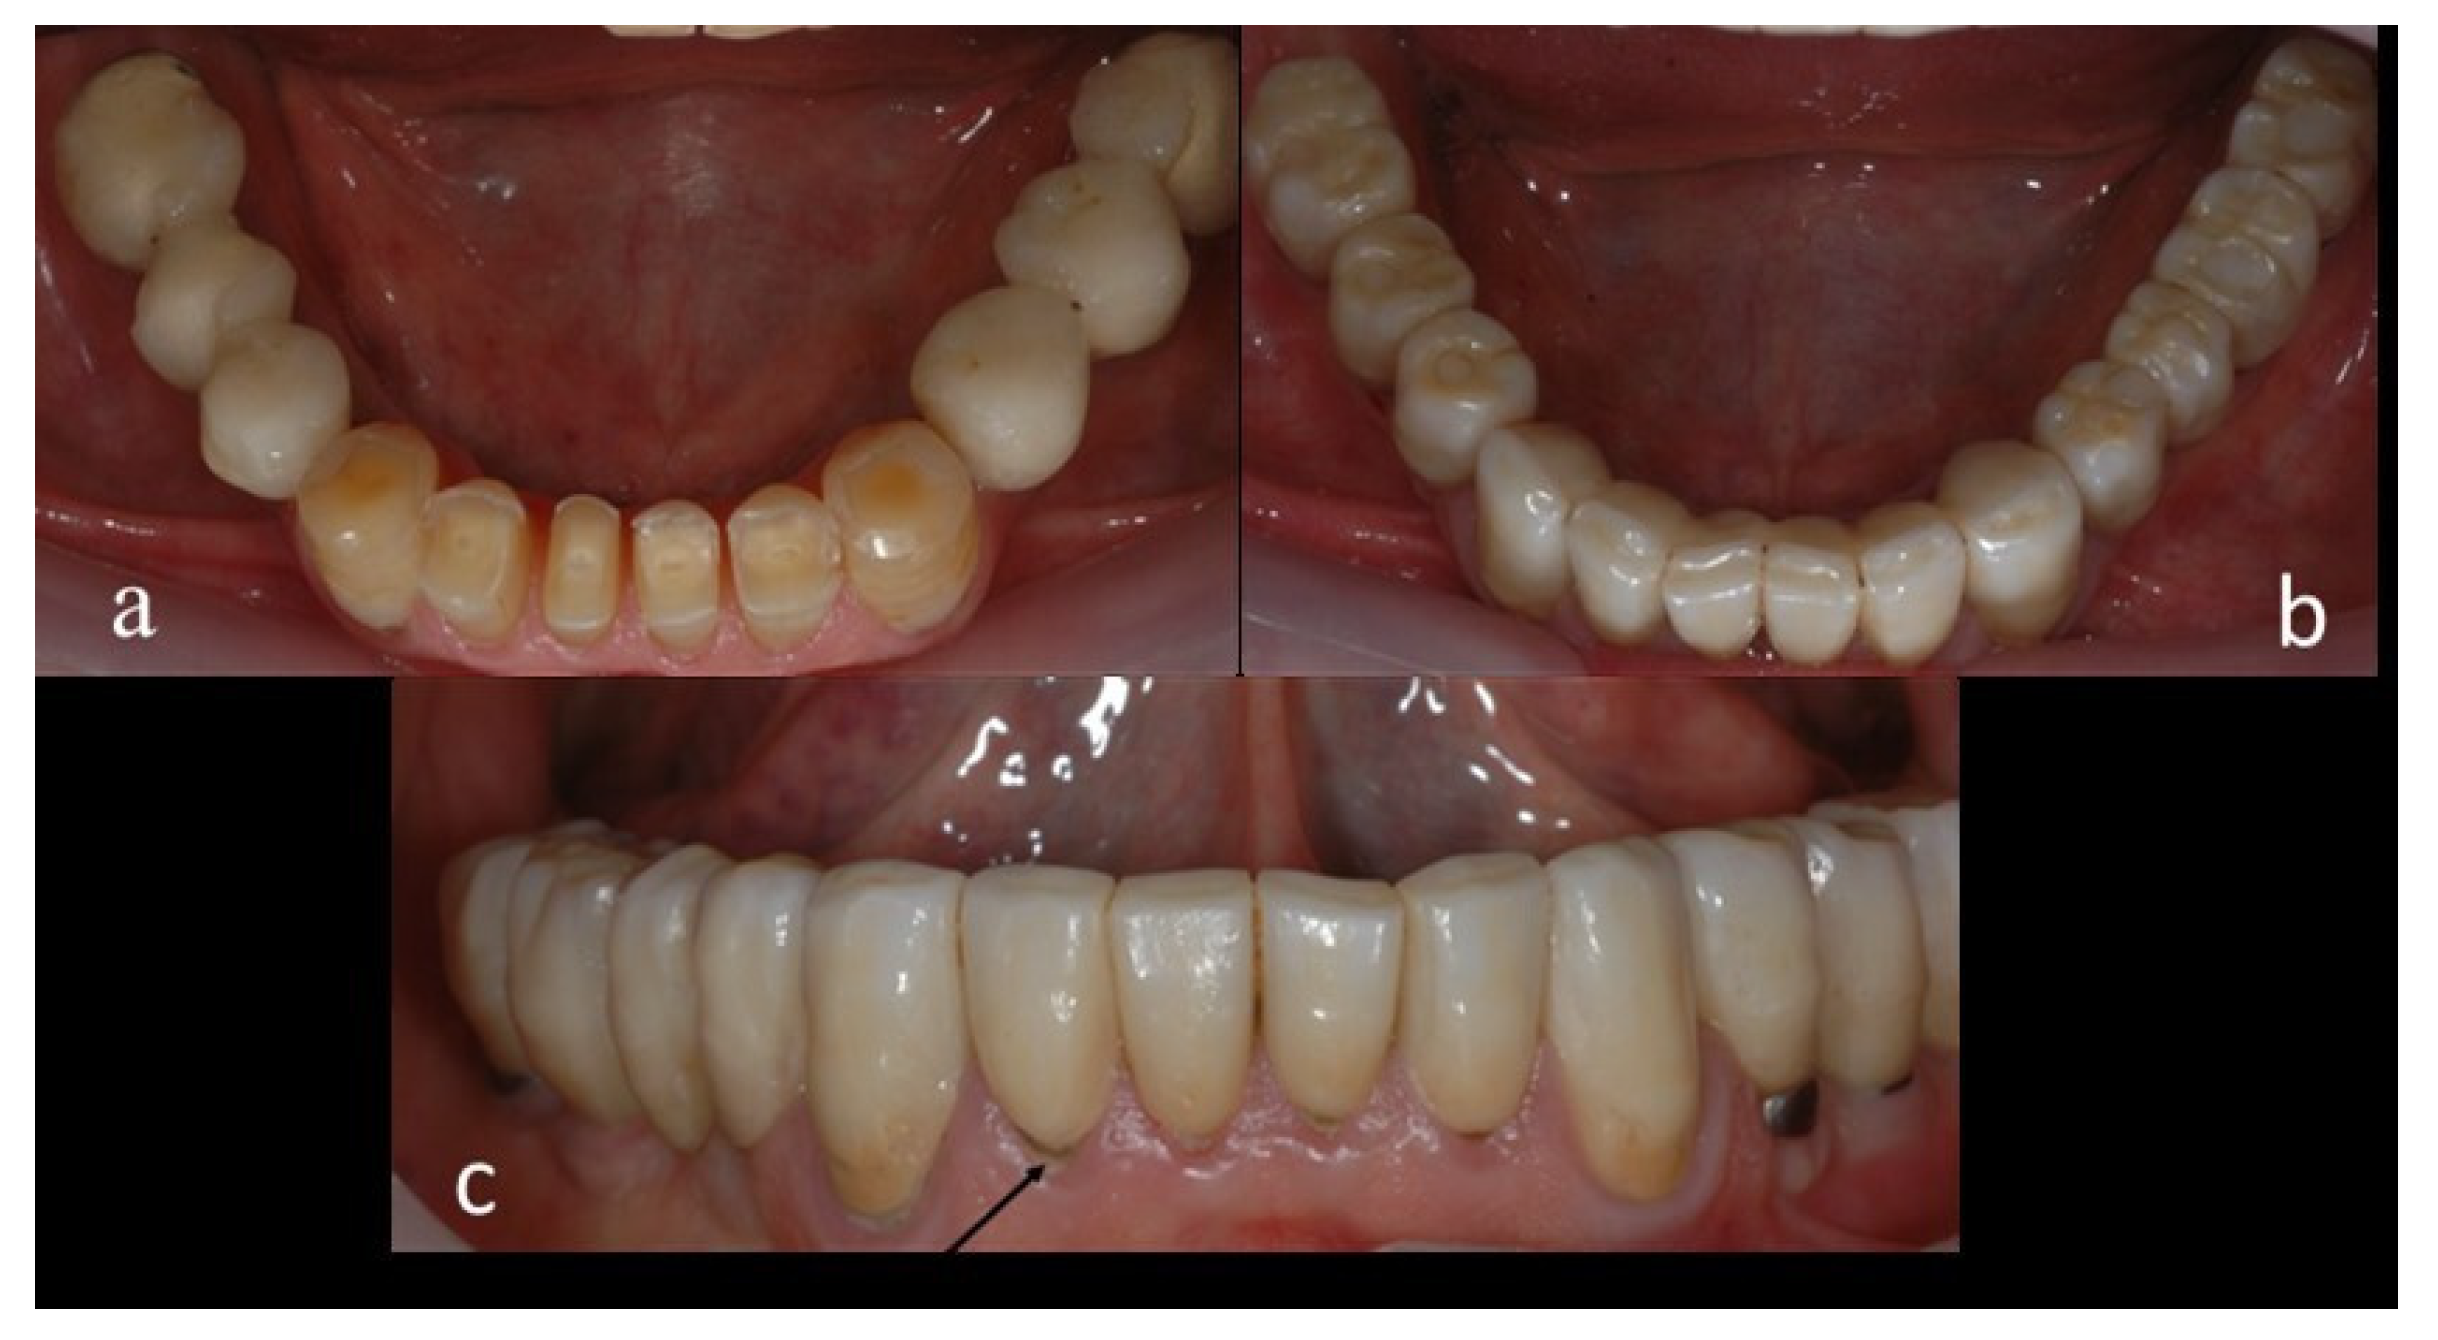

2. Materials and Methods

2.4. Methods

2.5. Clinical and Radiographic Assessments and Classification of Observed Events at the Recall Appointment